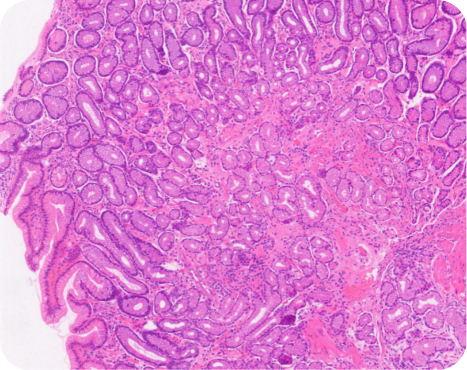

由资深病理科主任领衔,联合美国知名病理学专家共同组成强大的病理诊断团队,遵循国际标准的CAP质量管理体系,准确、及时地为国内外医疗机构出具高质量的中英文病理诊断报告。

实验室配备了全套进口的病理检验设备,提供各种组织病理学,细胞病理学检查服务,采用常规染色、特殊染色、免疫组织化学、荧光原位杂交等多项技术作为辅诊手段,为各类疾病的精准诊断和分型、肿瘤靶向药物治疗指导、疗效预测等提供可靠依据。

组织病理学诊断提供外科手术标本和活检标本的病理学检查服务,包含:内镜组织活检检查、局部切除组织活检检查与诊断、手术标本检查与诊断、穿刺组织活检与诊断等。